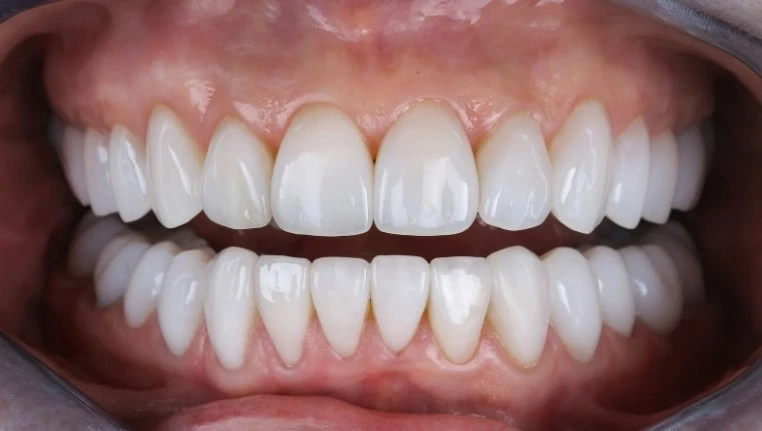

Вопрос восстановления зубов актуален для жителей Алматы не только с эстетической, но и с медицинской точки зрения. Современные методы позволяют вернуть красивую улыбку, однако истинная ценность имплантации проявляется гораздо глубже – она влияет на общее самочувствие, здоровье желудочно-кишечного тракта и даже на качество жизни. Многие ошибочно считают, что основная цель зубных имплантов – это привлекательный внешний вид, однако стоматологи давно утверждают обратное: восстановление зубного ряда необходимо для профилактики различных нарушений в организме. Например, на сайте компании Benefakta Dental зубная клиника Алматы предлагает своим пациентам не только эстетические услуги, но и комплексные решения для здоровья полости рта. Современная стоматология в Алматы развивается стремительными темпами: здесь применяют инновационные технологии, которые помогают восстановить жевательную функцию, предотвратить атрофию костной ткани и сохранить гармонию всей челюстно-лицевой системы. По оценкам специалистов, длительное отсутствие зубов может привести к осложнениям, которые сказываются не только на внешности, но и на работе внутренних органов. Именно поэтому важно рассматривать имплантацию не как исключительно косметическую процедуру, а как элемент заботы о своем здоровье, особенно в мегаполисе, где качество жизни напрямую зависит от самочувствия.

Имплантация зубов в современных условиях – это не просто замещение отсутствующих зубов. Применение имплантов позволяет восстановить утраченные функции, обеспечить правильную нагрузку на челюсть и предупредить дальнейшие патологии. К тому же, жевательная эффективность при использовании имплантов практически не отличается от естественных зубов, что важно для полноценного питания и профилактики пищевых расстройств.

Имплантация зубов позволяет восстановить анатомическую целостность зубного ряда и вернуть возможность полноценного, качественного пережёвывания. Благодаря внедрению современных технологий восстановленные зубы по своей функции практически не отличаются от натуральных, что существенно снижает риски для системы пищеварения.

Современная стоматология в Алматы давно перестала быть сугубо медицинской дисциплиной – она влияет на качество жизни, уровень коммуникабельности, успешность в профессиональной сфере. Эстетически совершенная улыбка заметно повышает самооценку, помогает преодолевать стеснительность и барьеры в общении. Однако за этими внешними изменениями скрываются глубокие психологические процессы, напрямую связанные со здоровьем.

Имплантация зубов даёт возможность вернуть не только полноценную функцию зубочелюстной системы, но и психологический комфорт. Пациенты отмечают уменьшение тревожности, повышение уверенности в себе, готовность к новым знакомствам и возможностям. Для многих восстановление зубного ряда становится толчком к переменам в жизни, появлению позитивных привычек, заботе о здоровье.